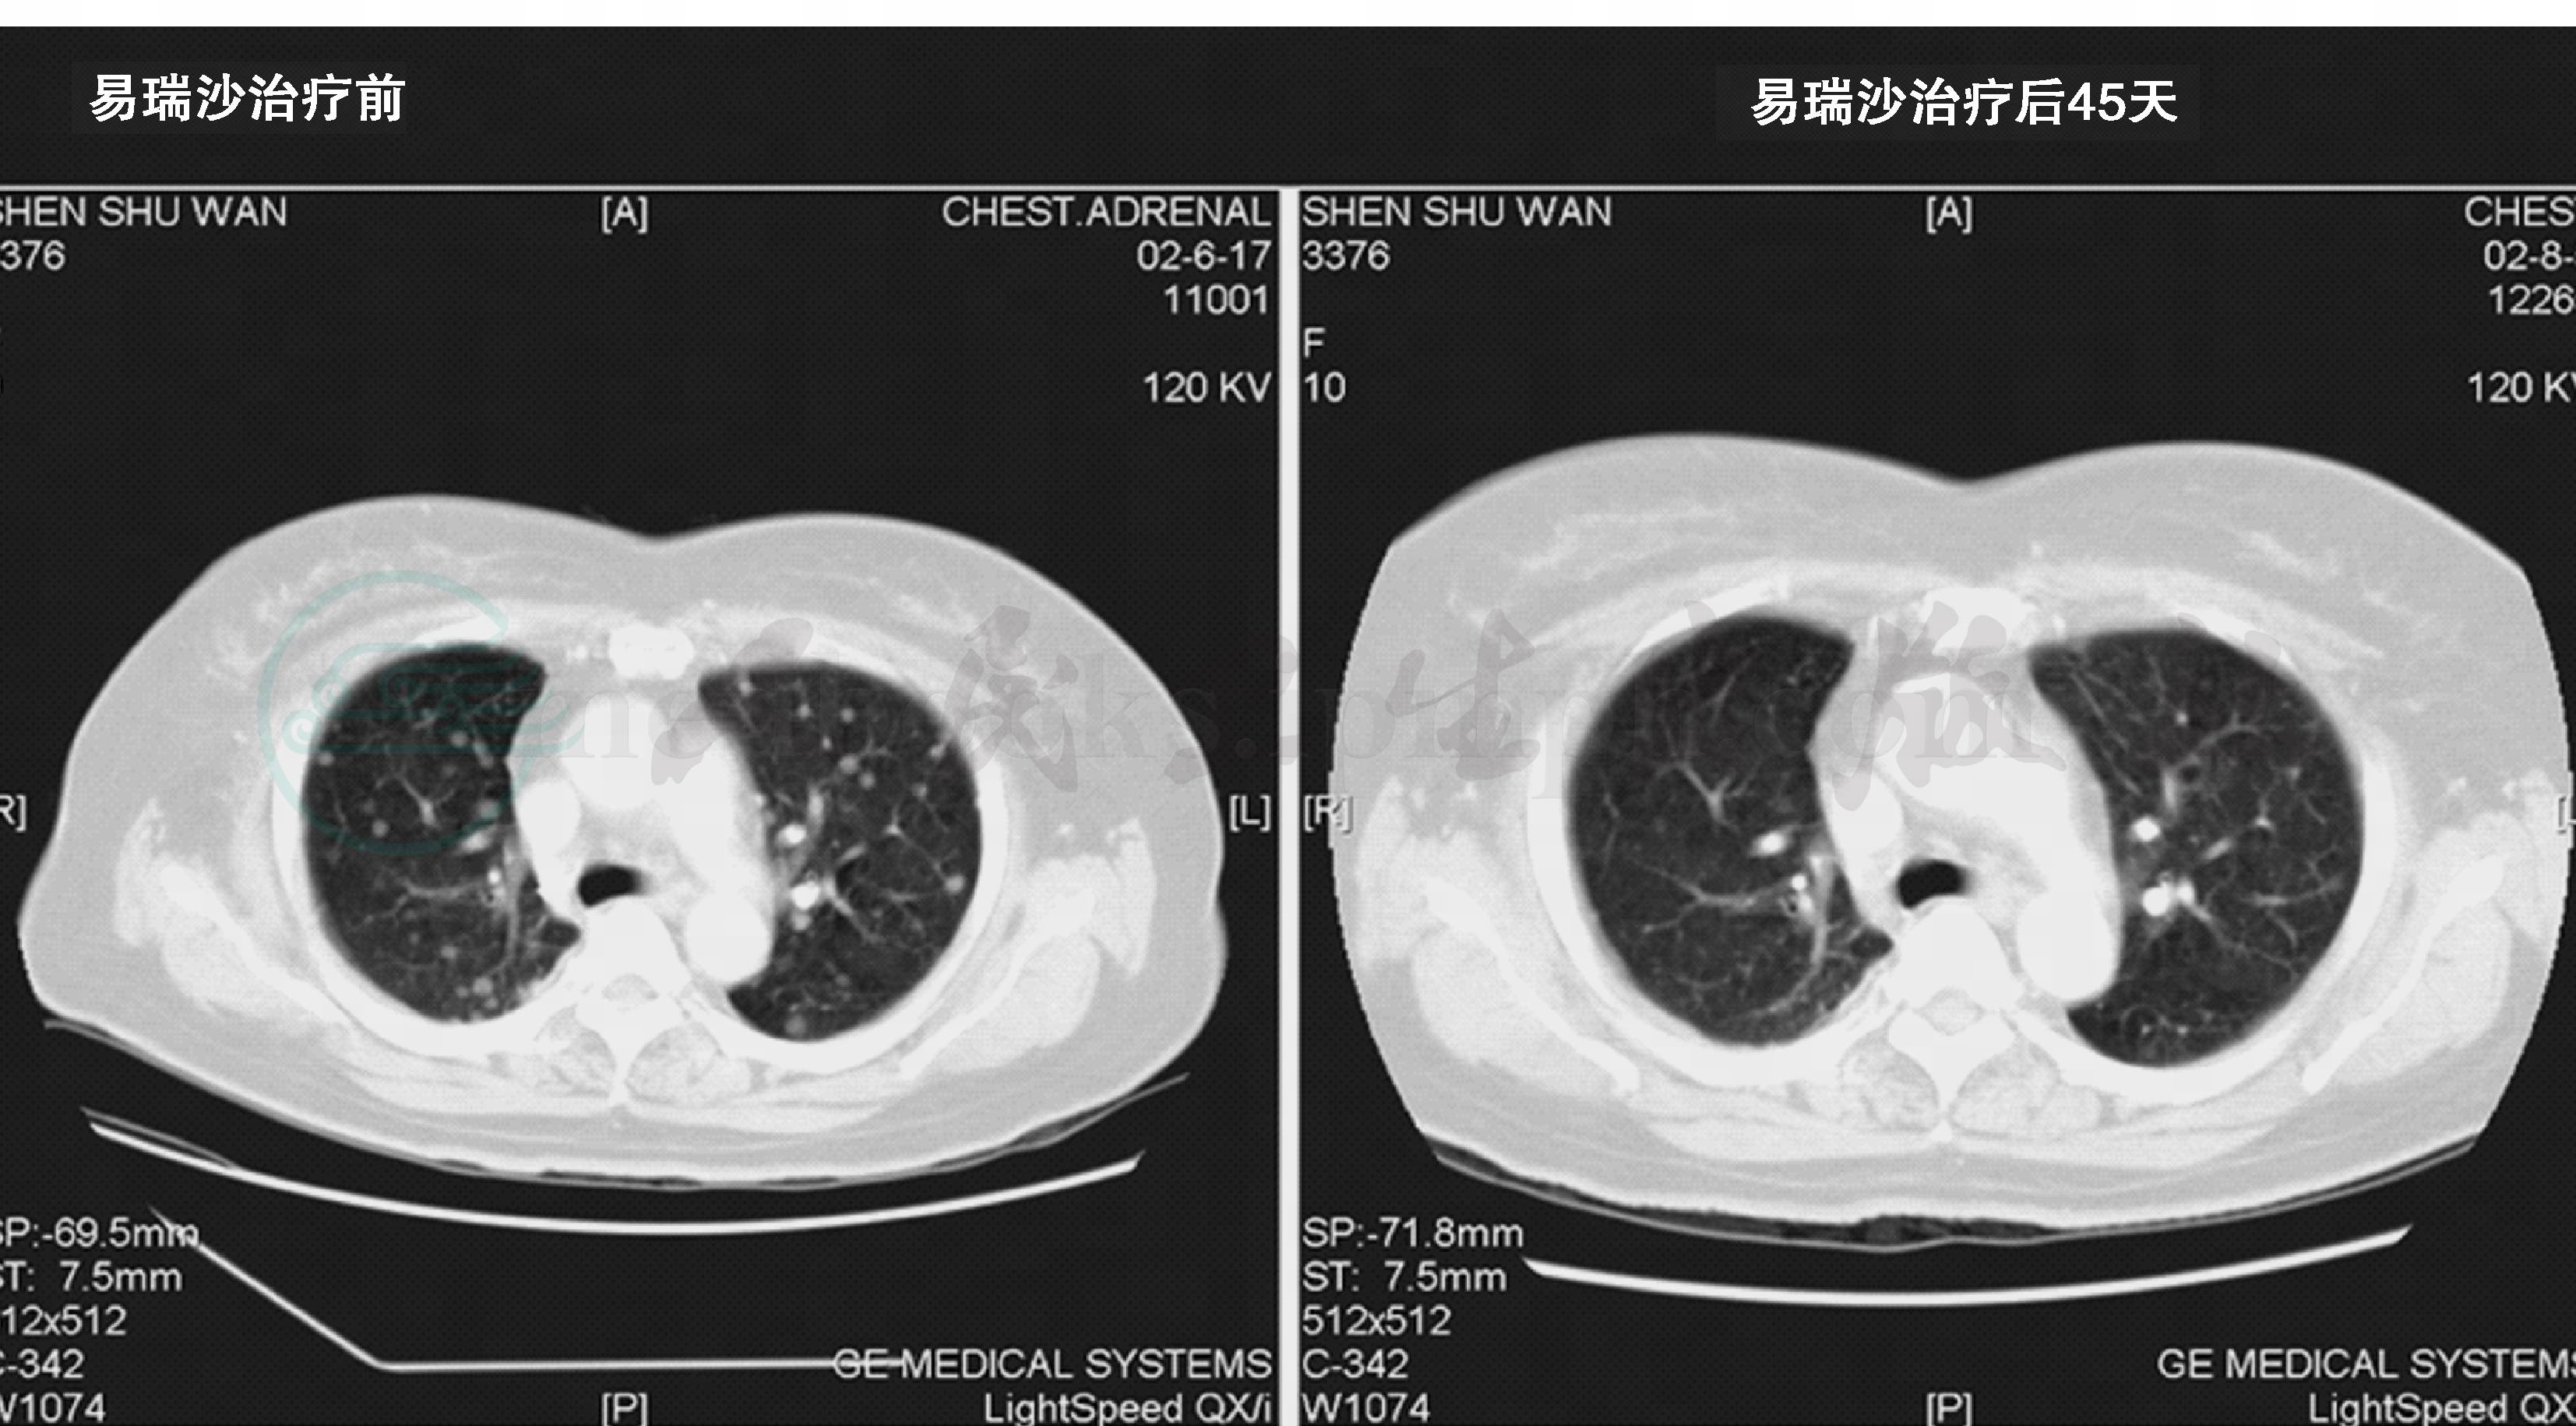

单纯的或完全性的细支气管肺泡癌(purebronchioloalveolarcarcinoma,pureBAC)是一种极其惰性、生长缓慢的类型(约占所有肺癌的4%),预后良好,五年生存率接近100%;而弥漫性细支气管肺泡癌则往往源于多原发肺腺癌合并不同比例BAC成分,以往被认为是一种预后不良的肺癌。直至20世纪末,传统定义的弥漫性细支气管肺泡癌作为一种不治之症,从咳嗽大量白色泡沫样痰,最终发展至弥散功能障碍而缺氧窒息,肿瘤专科医生对其爱莫能助。弥漫性BAC对化疗放疗均不敏感,肺移植在其中的作用仍需时间的进一步验证,而自从小分子表皮生长因子受体酪氨酸激酶抑制剂(epi‐dermalgrowthfactorreceptor‐tyrosinekinaseinhibitor,EGFR‐TKI)问世之后,给这部分患者带来了生机。图4为国内2001年较早期获益于EGFR‐TKI的一例女性、非吸烟、双肺弥漫性BAC伴EGFR21外显子L858R点突变的患者,服药45天后双肺多发病灶达完全缓解(completeremission,CR),两年后虽然出现继发性耐药并进展,但随访至2008年9月仍存活。

图4 弥漫性细支气管肺泡癌患者服用gefitinib45天后达完全缓解